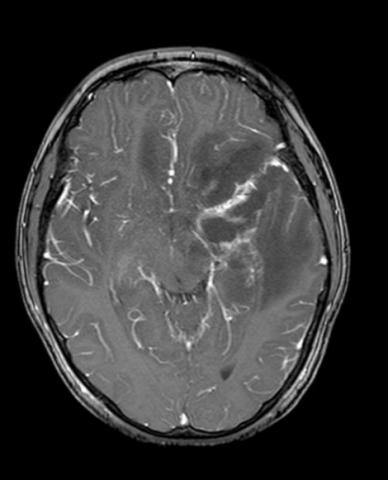

Intracerebral hemorrhage of basal ganglia, surgical management through transinsular transylvian approach. case report

GIUSEPPE ROJAS P.1a, JESÚS FLORES Q.2b